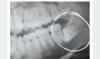

Полностью лежачий и половина под десной

Обезболили , пилили и вытаскивали по частям